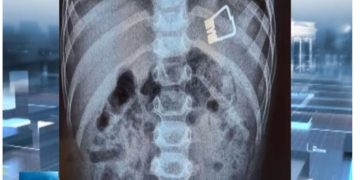

Μια μεγάλη περιπέτεια πέρασαν ένα αγοράκι δυο ετών και η οικογένειά του στη Λήμνο, όταν το παιδί κατάπιε ένα μανταλάκι και χρειάστηκε να διακομιστεί στο Ιπποκράτειο Νοσοκομείο στη Θεσσαλονίκη.

Οι γιατροί κατάφεραν να βγάλουν το μανταλάκι από τον οργανισμό του παιδιού χωρίς χειρουργική επέμβαση, παρά με τη βοήθεια ενός ενδοσκοπίου τελευταίας γενιάς.

Σύμφωνα με το ρεπορτάζ της ΕΡΤ, το παιδί κατάπιε το μανταλάκι στο σπίτι του και στη συνέχεια μεταφέρθηκε με Super Puma από τη Λήμνο στη Θεσσαλονίκη, όπου το ανέλαβαν οι παιδίατροι.

«Όταν το παιδί έφτασε εδώ αμέσως κινητοποιηθήκαμε, ενημερώσαμε τους αναισθησιολόγους, είχαμε έτοιμο το χειρουργικό κρεβάτι. Το παιδί έπρεπε είναι νηστικό 6 με 8 ώρες και προβήκαμε στην αφαίρεση ενδοσκοπικά του ξένου σώματος», δήλωσε ο Ιωάννης Ξηνίας, αναπληρωτής καθηγητής Παιδιατρικής Γαστρεντερολογίας.